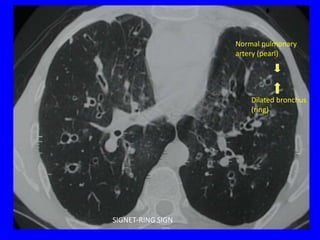

THE CT SCAN

•   Signet ring sign

•   Tram-tracks

•   String of beads

•   Circles filled with air or air and fluid

•   Tubular and branching opacities

•   Bronchi visible within 1 cm of the pleura

Normal pulmonary

artery (pearl)

Dilated bronchus

(ring)

SIGNET-RING SIGN